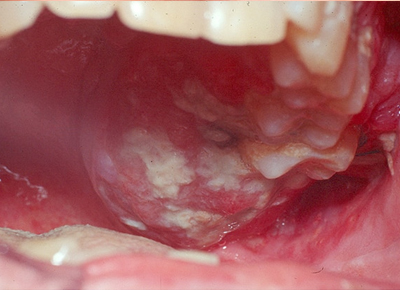

- Oral cancer. Oral cancer can present on the tongue in several ways. Tongue cancer symptoms may include pain or an ulcer that does not heal within two weeks.Alternatively, cancerous spots may be painless and can present in many forms, such as difficulty moving the tongue or white or red patches that do not heal.

COVID tongue consists of ulcers and white patches in the mouth, specifically on the tongue. As this is a new phenomenon, there is no current medical definition and is instead being referred to as such. Researchers in Madrid dubbed the new term after conducting a field hospital study and discovering 25% of the 666 patients with mild to moderate cases of COVID presented bumps, ulcers, white coating, and inflammation of the tongue. They specified that the symptoms are not always consistent, and there are various forms of “COVID tongue.”

Another study, published in June 2020 in the Nature Journal Evidence-Based Dentistry, suggested a link between oral ulcers, blisters, and COVID. The researchers believe these symptoms have gone undetected due to a lack of intraoral examination. A similar study published in JAMA Dermatology in July 2020 expressed similar findings and believed oral manifestations go unnoticed as those with COVID concerns are not being examined.

Many of the researchers cited here stressed the importance of increasing intra-oral examinations in COVID patients. Dental professionals cannot assume that ulcers, blisters, and discoloration in the mouth result from COVID; however, the increasing prevalence of these oral manifestations highlights the importance of intraoral examination and the potential to identify the disease before definitive diagnosis.